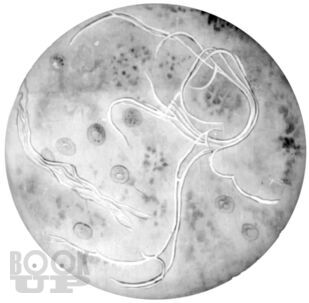

В руководстве для врачей излагаются вопросы истории становления противотуберкулезной службы в России, представлены сведения по микробиологии, эпидемиологии и фундаментальные данные во фтизиопульмонологии. Подробно рассмотрены клинические формы туберкулеза органов дыхания, синдромная диагностика и синдромная дифференциальная диагностика туберкулеза органов дыхания, вопросы саркоидоза в работе фтизиатра и терапевта. Обращено внимание на основные осложнения туберкулеза и оказание помощи при них, коморбидную патологию, современное этиопатогенетическое лечение больных туберкулезом, в том числе с использованием авторских индивидуальных методов активационной патогенетической терапии. Особое место в книге занимают вопросы профилактики и организации борьбы с эндемией туберкулеза. Руководство предназначено для врачейфтизиатров, рентгенологов, терапевтов и инфекционистов, а также для студентов высших медицинских учебных заведений по специальностям «Лечебное дело», «Педиатрия» и «Профилактическое дело».